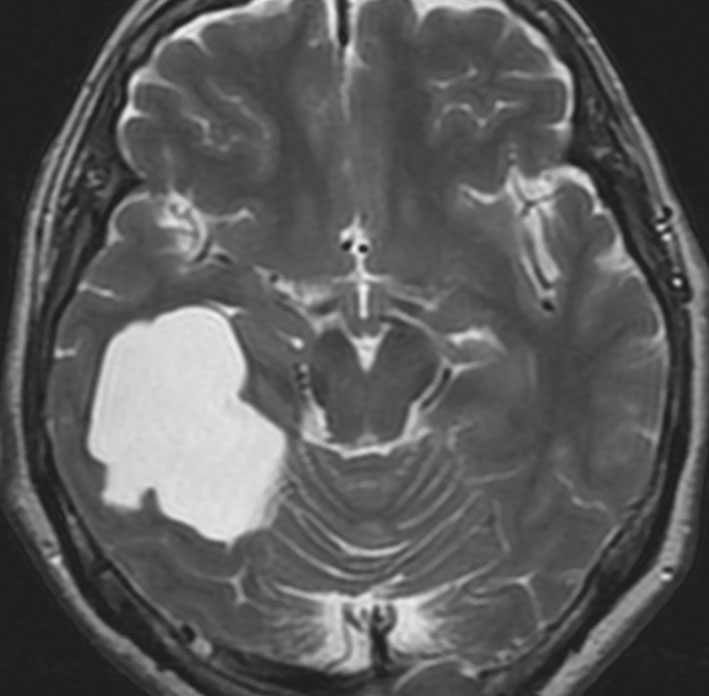

中頭蓋窩・症候性・くも膜のう胞

60代の女性で偶然発見された大きなクモ膜のう胞です。経過とともに少しづつ増大して,ふらつき,眠気,気分の落ち込みなど抑うつ状態となりました。抗うつ薬の投与が開始され増量されましたが精神症状は悪化して何もできなくなりました。おそらく右側頭葉症状として抑うつ症です。内視鏡ですと脳に損傷が生じますから,開頭顕微鏡手術で,クモ膜のう胞を脳底槽へ開窓しました。術後に症状は消失して5年になりますが,抗うつ薬なしで元気にしています。

もしかするとこれは,巨大な choroidal fissure cystかもしれません。